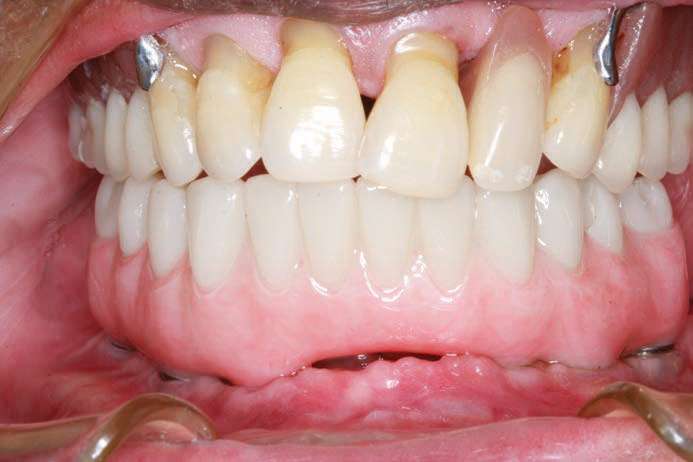

A wax-rim was sent for recording a maxilla-mandibular jaw registration (Figure 15), and then teeth were set, and a wax set-up (Glidewell Laboratories) was returned to evaluate phonetics, aesthetics, and verti-centric (Figure 16). A PMMA provisional implant prosthesis was fabricated and delivered, giving the patient an opportunity to verify the prosthetic design, aesthetics, and phonetics during function (Figure 17).

At this time, the patient suffered a stroke and lost some of the dexterity in his hands. It became evident when observing the patient’s difficulty in cleaning the PMMA provisional implant prosthesis, that he would require help from his wife. In addition, the gingival embrasures would need to be opened up more to allow for easier access with at-home cleaning aids (such as GUM Proxabrush Go-Betweens Cleaners [Sunstar Americas] and Waterpik). Instructions for these prosthetic design modifications were submitted to the dental lab, which sent updated CAD design images for clinician approval, prior to finalization of the prosthesis. After review, the digital design was modified until we had a cleansable gingival surface for the BruxZir Solid Zirconia Full-Arch Implant Prosthesis (Figures 18a to 18d). An additional PMMA provisional implant prosthesis was fabricated and delivered to confirm these final design changes; it had an almost Roman aqueduct appearance to the gingival surface of the prosthesis (Figure 19).

The final monolithic zirconia restoration was fabricated based on the same digital design as the approved PMMA provisional, allowing the patient and his wife easy access for all cleaning implements. The patient had little food impaction and was comfortable with his border movements and ability to really cut and chew his food.